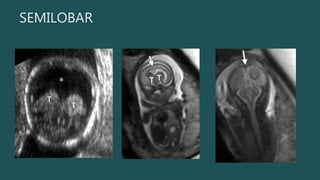

SEMILOBAR

Semilobar y Lobar El único hallazgo obvio por US a las 18-20 sdg sería la incapacidad de detectar el cavum septum pellucidum. • La malformación es semilobar si los lóbulos frontales están fusionados > 50%. • Hoz y fisura interhemisférica posterior y parte posterior del cuerpo calloso Hipotálamo y tálamo siempre fusionados SEMILOBAR

• #19 El diagnóstico prenatal de HPE alobar es bastante sencillo Semilobar y lobar pueden ser un desafío. In semilobar HPE, the interhemispheric fissure and falx cerebri may be present posteriorly and part of the corpus callosum may be seen in the region of the posteriorly sepa rated hemispheres , with the anterior extent corresponding to that of the interhemispheric fissure. somewhat arbitrary criterion used in postnatal imaging is that the malformation is semilobar if the frontal lobes are more than 50% fused

• #20 Semilobar HPE. (a) Axial oblique US image shows a continuous mantle of brain anteriorly (arrowheads) but posterior division into hemispheres (arrows). (b) More inferior axial US image in the same patient shows normal posterior fossa structures (arrow) below the tentorium but fused anterior supratentorial brain (arrowheads).

• #21 Semilobar HPE. (a) Coronal US image shows a monoventricle (*) and partial fusion of the thalami (T). (b) Coronal T2-weighted half-Fourier RARE MR image shows the continuous anterior brain parenchyma (arrow), monoventricle (*), and partially fused thalami (T). (c) Coronal T2-weighted half-Fourier RARE MR image more posteriorly shows two occipital lobes separated by the falx (arrow).